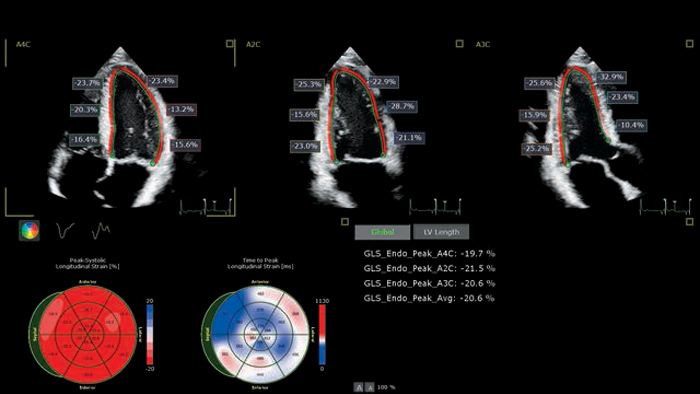

Cardio-oncology guidelines

prescribe the use of Cardiac

Imaging modalities

Cardiac imaging modalities support a more confident stratification of cardiovascular toxicity while serving as a powerful baseline reference for treatment and long-term follow-up.

To read the complete 2022 ESC guidelines for cardio-oncology visit our cardiotoxicity page.